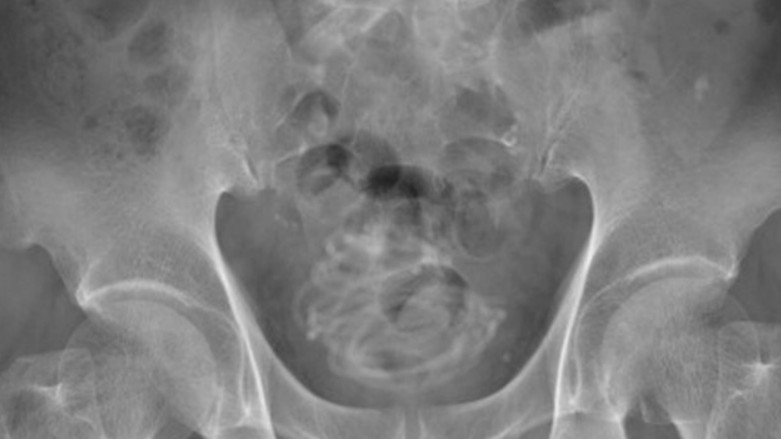

Um homem, de 79 anos, procurou um hospital após sentir fortes dores ao urinar. Na unidade de saúde, os médicos realizaram um exame de raio-X e...